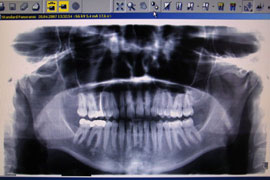

Digitales Röntgen ist ein bildgebendes Verfahren, bei dem nicht ein herkömmlicher Röntgenfilm belichtet wird, sondern eine spezielle Folie oder ein Röntgensensor die von einem Computer abgenommen werden. Das Röntgenbild kann anschließend auf dem Monitor sichtbar gemacht werden.

Digitales Röntgen wird in der Zahnmedizin zur Diagnose und zur Verlaufskontrolle vorgenommen. Besonders bei Karies kann digitales Röntgen erkrankte Stellen sichtbar machen, die bei normaler Betrachtung im Mund noch nicht erkennbar sind. Auch vor Behandlung der Parodontitis, bei einer Wurzelbehandlung und vor Einsetzen von Kronen oder dem Ziehen von Zähnen ist das Anfertigen einer Röntgenaufnahme eine wertvolle Hilfestellung. Es können einzelne Zähnen, begrenzte Kieferbereiche, aber auch eine umfassende, so genannte Panoramaaufnahme (OPG) angefertigt werden.